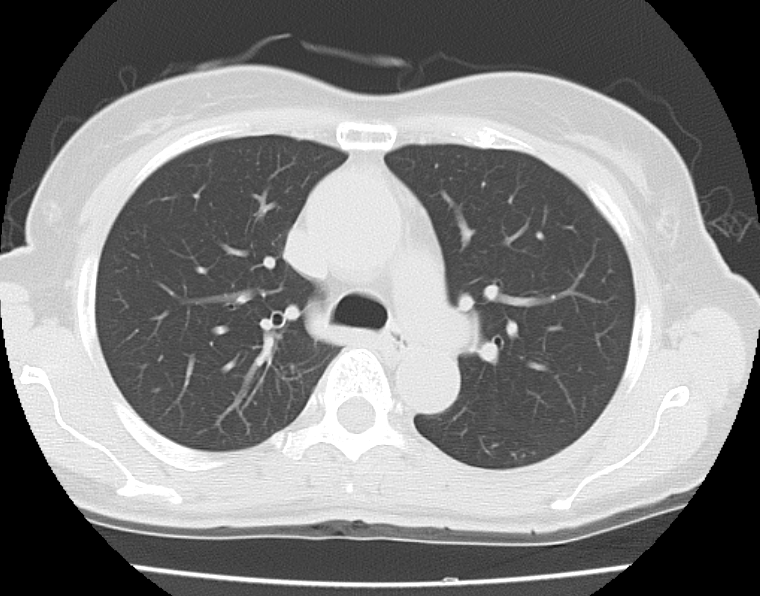

CTはドーナツ状の筒があり、体がこの筒を通る際にX線を体に照射し、撮影を行います。 この時、体の中の成分によってX線の通り抜ける量が変わります。密度の⾼い⾻などはX線が通り抜けにくく、画像では⽩く映ります。反対に、空気が多く密度が低い肺などはX線が通り抜けやすく、画像では黒く映ります。このX線の通り抜ける量の差を画像化することで、普段よくみられるCT画像となります。

撮影された画像データを⽤いて、様々な⾓度から体を観察できます。よく使われるのは、体を横からみた⽮状断(サジタール画像)、体を正⾯からみた冠状断(コロナール画像)です。また3D画像も作成可能です。⼿術や検査結果の説明に使⽤されています。